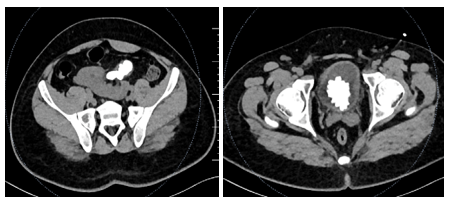

A 27-year-old male presented with suprapubic pain, dysuria, and intermittent haematuria for 7 days. X-ray KUB revealed a bladder calculus, while ultrasound suggested a pelvic fused kidney with renal stones (Figure 1).

Figure 1:- Large Vesical calculus seen in X-Ray KUB.

Contrast-enhanced CT KUB demonstrated a single, flat, discoid renal mass located in the pelvic cavity, consistent with a pancake kidney, showing complete fusion of both renal units across the midline with absent renal ascent and malrotation. The collecting systems were anteriorly oriented and the ureters were observed to be short. Within the fused renal moiety, two non-obstructing calculi were identified, measuring approximately 10.8 × 11.7 × 16.3 mm and 7 × 9 × 9.5 mm. There was no associated calyceal dilatation or hydronephrosis. Additionally, a large hyperdense vesical calculus was noted within the urinary bladder (Figure 2).